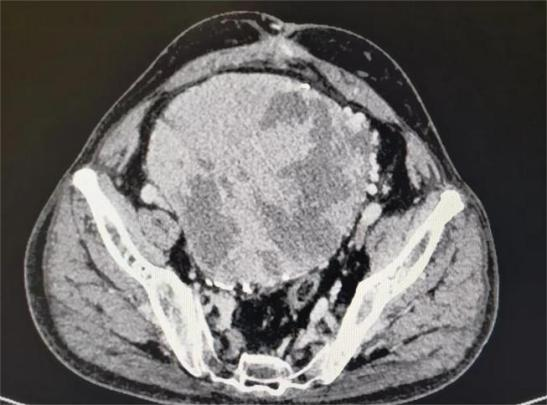

术前影像学:占位范围广、周围比邻多支神经血管